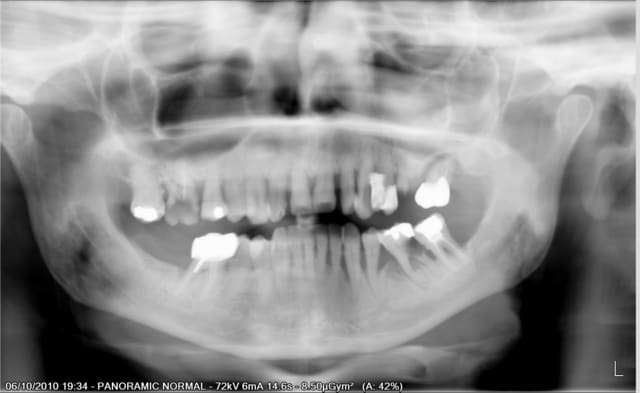

Patiente qui se presente au cabinet car ne supporte plus ses dents.

Elle fume 1 paquet par jour.

Pour le maxillaire je lui ai proposé de faire 4 implants + locator + PTotale

ou 6 implants + prothése fixe ( type pilotis). Au choix de la patiente.

Par contre pour la mandibule je sèche un peu.

Est ce que je garde des dents ou pas?

Je pensais peut être garder de 46 à 33 avec assainissement paro et pose de 2 implants en 34/36 avec bridge sur implant.

Ou alors j'extrais tout et je fais une prothése implanto portée?

La patiente le sait, le traitement ne pourra être entamé que si elle stoppe ou diminue fortement sa consommation de tabac.